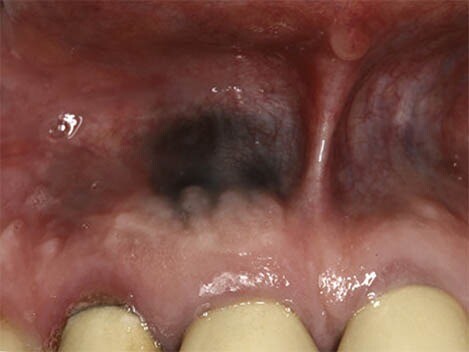

What Causes a Black Spot on Your Gums?

First, we recommend taking a moment to breathe and relax. According to the Oral Cancer Foundation, dark spots rarely indicate a serious condition like cancer and are usually benign. Spots in the mouth are often not fully black but may appear that way as they can be hard to see. We’re here to help walk you through the causes of dark spots in your mouth and what they mean.

Oral conditions like dark spots on your gums have various causes and can be challenging to diagnose. These spots can either be harmless or the result of an underlying disease, so it's essential to speak to your doctor if you believe you have any symptoms.

What exactly causes black spots on your gums? There are two categories of answers: those with internal causes and those with external causes.

Internal pigments that cause skin colour changes can also modify your gums' colour to black, grey, blue, or brown. Blood vessels can even dysfunction or rupture, leading to discolouration.

According to a research article published in the Journal of Indian Academy of Oral Medicine and Radiology, haemangiomas are most common soft tissue benign tumours, composed of blood vessels, and occur in the head and neck region (60%) and less commonly in the oral cavity; oral cavity if affected involves gingiva followed by the lips, tongue and palate.

In rare cases, benign lesions that don't require treatment may transform into oral malignant melanoma, a type of oral cancer. A doctor will look at a range of factors to see if the lesion qualifies as melanoma. According to a research article published in the Journal of Indian Academy of Oral Medicine and Radiology, melanoma constitutes only 3–5% of all cutaneous malignancies, and oral melanoma is an aggressive neoplasm which accounts for less than 0.5%.